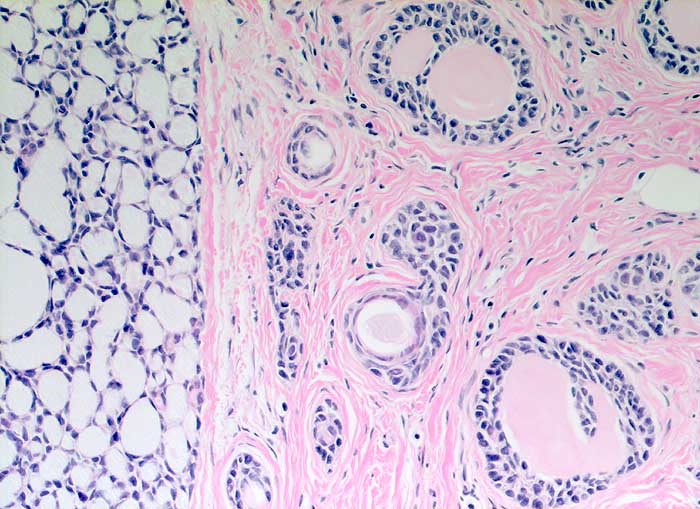

Einleitung

Adenoidzystische Karzinome machen lediglich 1% aller Mammakarzinome aus. Die Morphologie ist identisch mit dem gleichnamigen Tumor der Speicheldrüsen. Die Zellen des adenoidzystischen Karzinoms bilden kohäsive Verbände und Drüsen oder mikrozystische Strukturen. Die Tumorzellen sind klein und monomorph, die Kern-Zytoplasmarelation ist hoch. Die Kerne sind dunkel, rund bis oval oder angulär und enthalten bisweilen einen kleinen Nukleolus. Azelluläre hyaline Körperchen aus mucoidem Material, welche die Hohlräume der intakt aspirierten kribriformen Strukturen ausfüllen, sind besonders typisch. Das mucoide Material kann auch verzweigte oder fingerartige abgerundete Strukturen ausbilden.